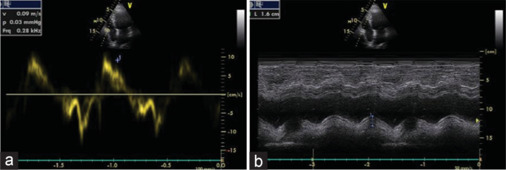

Results: Right ventricular basal diameter was significantly higher in groups chronic kidney disease (CKD) V and HD than control. Right ventricle tricuspid annular plane systolic excursion (RV TAPSE) and RV tissue Doppler imaging(S') were significantly lower in CKD Group V than HD and control group. Pulmonary HTN is present in 22% of renal patients with significantly higher prevalence in HD group. There was a positive correlation between the estimated glomerular filtration rate (eGFR) and RV TAPSE and between eGFR and RV (S') of CKD IV and CKD V groups. There was a negative correlation between RV TAPSE and pulmonary arterial systolic pressure by echocardiogram of the studied groups. There was a positive correlation between RV TAPSE and RV (S') of the studied groups.